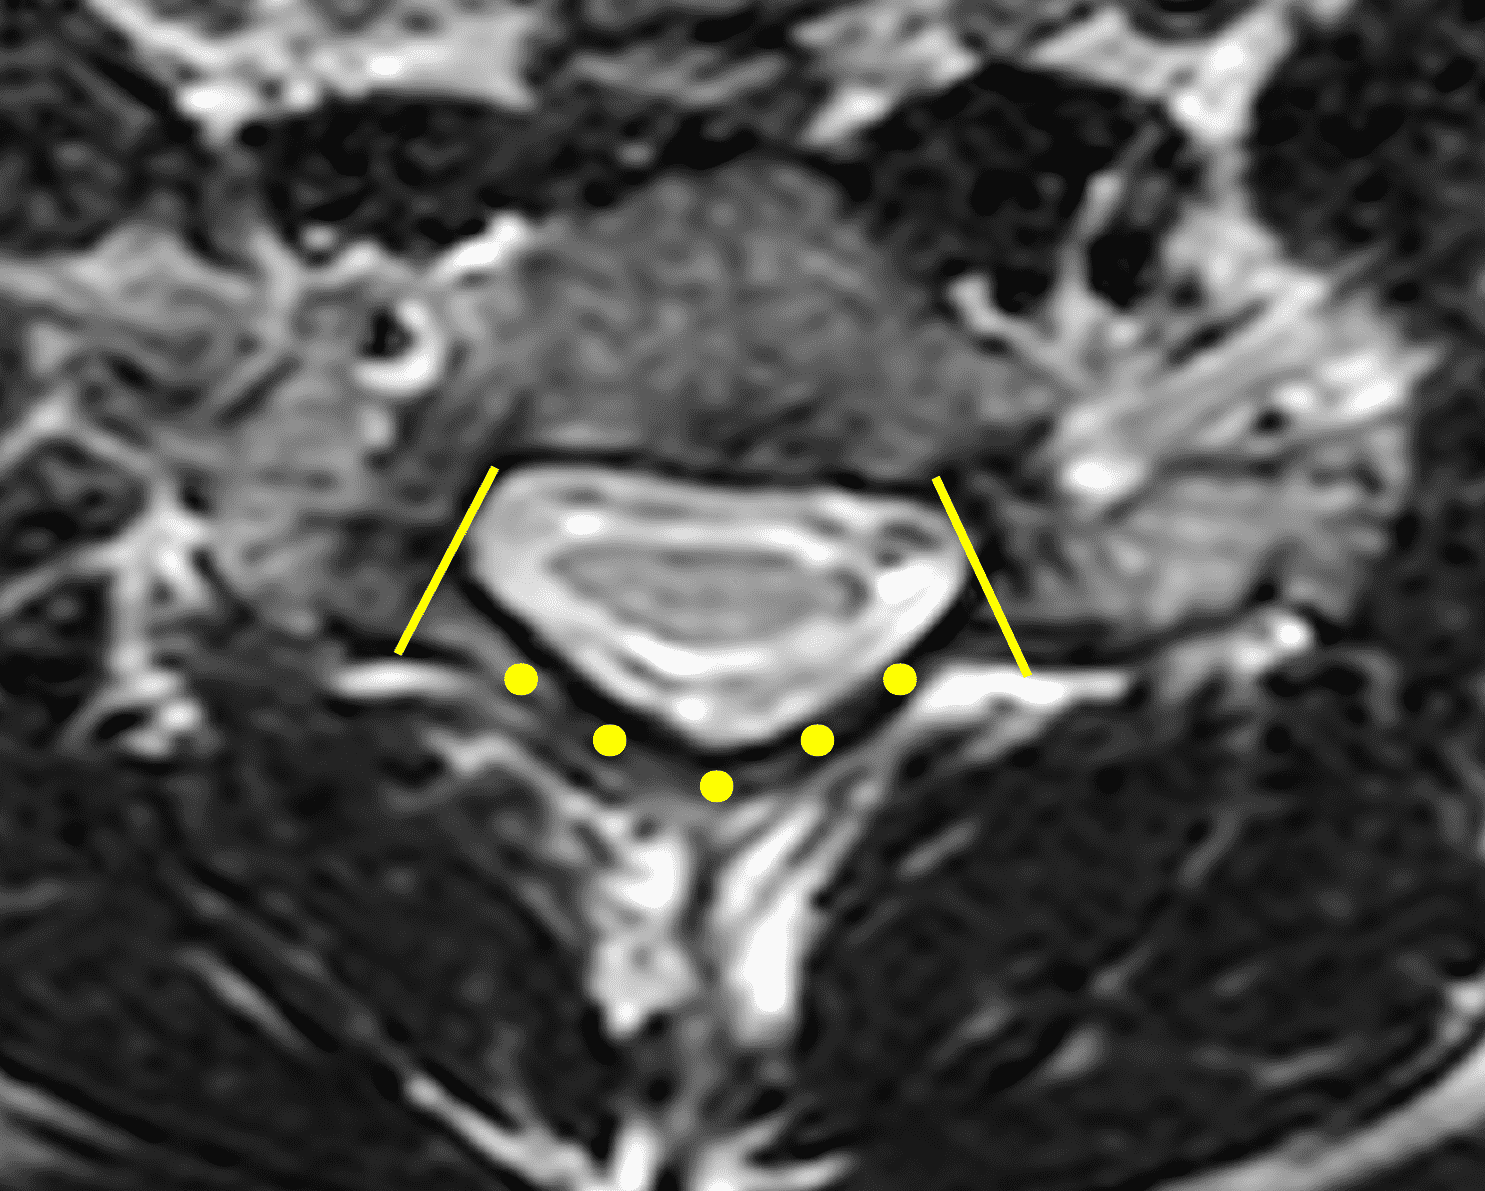

The LOA sign was proposed as a finding suggesting HD on neutral position MRI of the cervical spine.29 The degree of loss of attachment of the posterior dural sac and subjacent lamina are evaluated on each side of the lamina at C4 to C6 levels on axial T2-weighted images, with separation along more than one-third of the lamina on one or both sides considered positive for LOA. To assess the degree of LOA, the lamina is defined medially by the point of junction of the lamina and laterally by a tangential line along the medial aspect of the pedicle and then divided into three equal parts (Figure 6). The LOA sign was found to have a sensitivity of 93.5% and specificity of 98% for HD. The LOA sign was investigated in the first multisite North American study by Lehman et al.5 and found to have a lower sensitivity of 70% but similar specificity of 100%. The authors confirmed that the LOA sign and other findings are often present on neutral position MRI and in the appropriate clinical scenario, should raise suspicion and prompt further assessment by flexion MRI to confirm the diagnosis.

Figure 6: Axial images demonstrating the loss of attachment (LOA) sign. (6A) T2-weighted and (6B) T1-weighted images in a normal spine (same patient as Figure 3). Yellow lines mark the lateral extent of the laminae, which have been divided into thirds (yellow dots). The posterior dura (red arrows) is firmly attached to the lamina. (6C) T2-weighted and (6D) T1-weighted images of a spine with HD (same patient as Figure 1) show the lamina divided into three equal parts (yellow lines and dots) and displacement of the posterior dural sac, right greater than left, with loss of attachment (red arrows). The separation involves more than one-third of the length of the lamina on both sides.